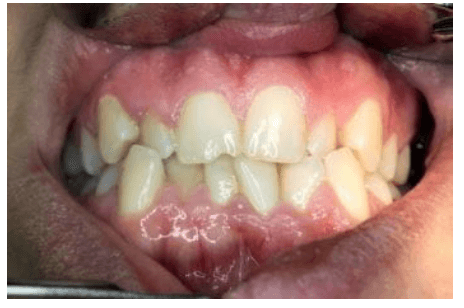

정상적인 교합은 입을 다물었을 때 상악치아가 하악치아의 바깥쪽을 전체적으로 살짝 덮는 모습입니다 정상교합은 안쪽으로 적절하게 교합이 이루어지기 때문에 치아의 중요한 역할인 음식을 씹을 때 씹는 힘이 균등해지며 효과적으로 씹을 수 있습니다 하지만 부정교합의 경우 힘이 균등하게 분배되지 않으며 치아가 비정상적으로 마모되어 치관 부분이 파절 되거나 치아손실이 일어날 수 있는데요 아래에서 부정교합의 정도에 따른 3단계를 알아보겠습니다

치아부정교합의 증상으로는 치아가 어긋나거나 교합이 이상한 경우, 치아가 불규칙적으로 배치되는 경우, 양쪽 턱끝이 맞지 않는 경우, 턱관절의 통증이나 불편감 등이 있습니다. 또한, 치아부정교합으로 인해 치아와 인접한 부위에 치주질환 등의 문제가 발생할 수도 있는데요 부정교합의 정도에 따라 3단계로 나누어집니다

| 1급 부정교합 | 겉으로 보여지는 모습은 문제가 없지만 덧니가 있거나 치열이 삐뚤거리거나 일부치아의 돌출,치아사이벌어짐등의 증상이 있습니다 |